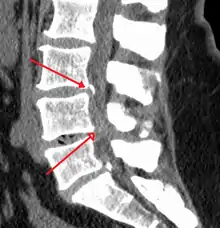

The diagnosis of spinal stenosis involves a complete evaluation of the spine. The process usually begins with a medical history and physical examination. X-ray and MRI scans are typically used to determine the extent and location of the nerve compression.

MRI

MRI has become the most frequently used study to diagnose spinal stenosis. The MRI uses electromagnetic signals to produce images of the spine. MRIs are helpful because they show more structures, including nerves, muscles, and ligaments than seen on X-rays or CT scans. MRIs are helpful in showing exactly what is causing spinal nerve compression.

Myelography

In CT myelography, spinal tap is performed in the low back with dye injected into the spinal fluid. X-rays are performed followed by a CT scan of the spine to help see narrowing of the spinal canal. This is a very effective study in cases of lateral recess stenosis. It is also necessary for patients in which MRI is contraindicated, such as those with implanted pacemakers.